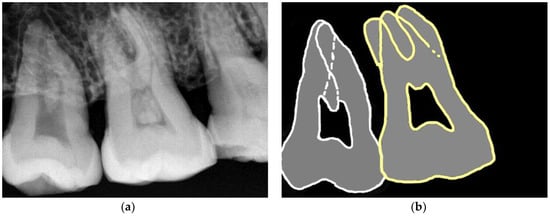

2.3. Measurements